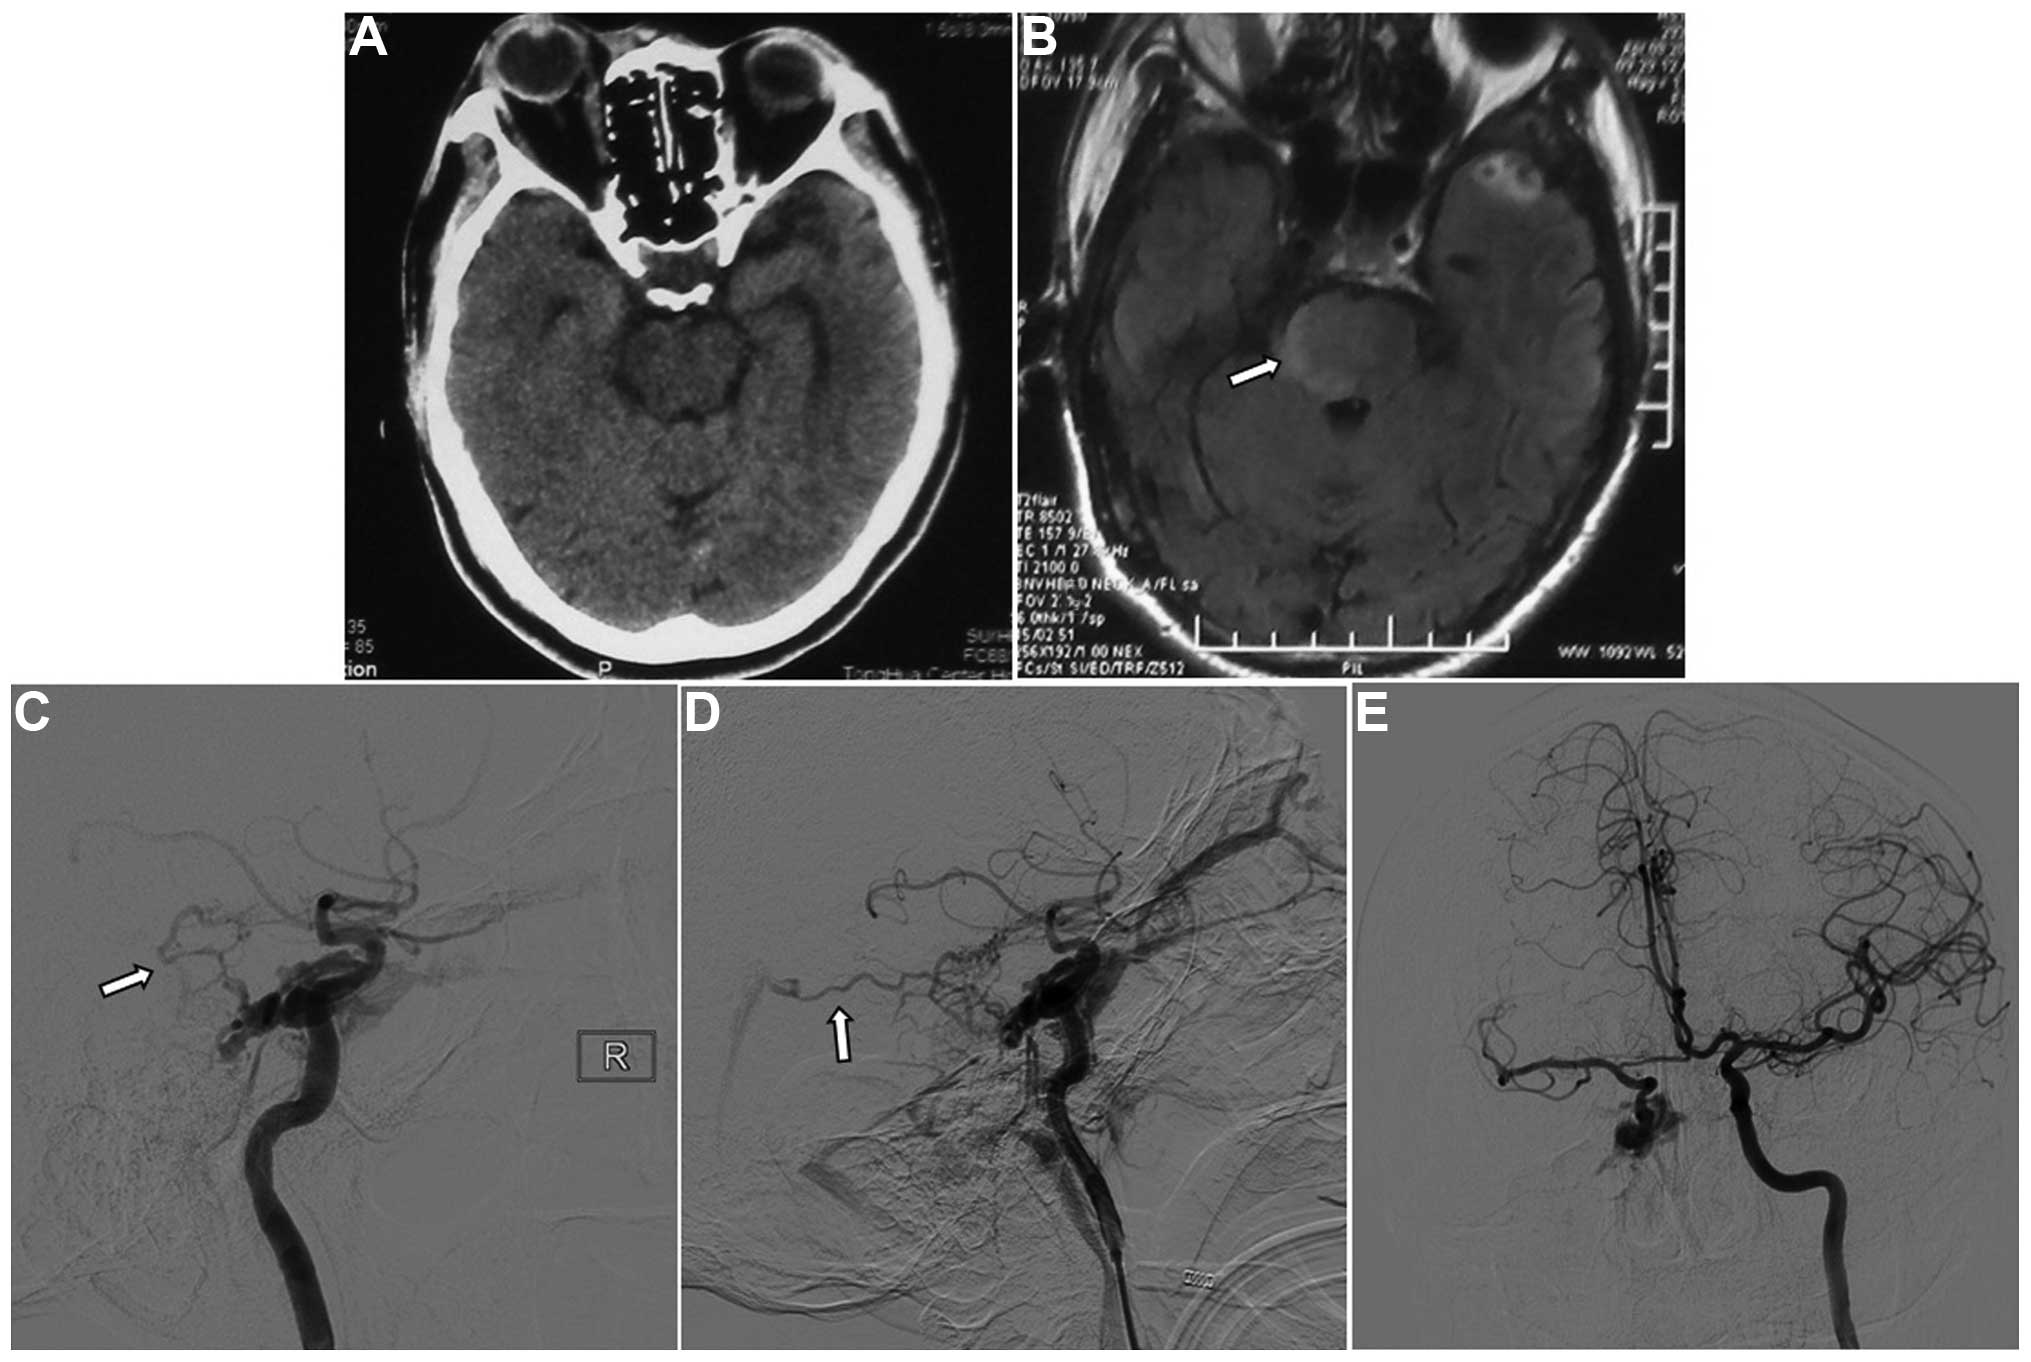

Brainstem edema caused by traumatic carotid-cavernous fistula: A case report and review of the literature

Brainstem edema caused by traumatic carotid-cavernous fistula (TCCF) is rare, and there is little information available regarding its clinical characteristics. The present report describes the case of a 51‑year‑old man with TCCF, who presented with right exophthalmos and intracranial bruit for 1 week. One month prior to admission at hospital, he fractured the frontal and ethmoid sinuses. Digital subtraction angiography confirmed the diagnosis of TCCF, and magnetic resonance imaging (MRI) suggested edema on the right side of the pons. Five days after admission, the patient exhibited left hemiparesis, and MRI revealed aggravation of the brainstem edema. Following treatment with transarterial balloon embolization, the clinical symptoms, including hemiparesis, were relieved; at the 1‑month follow‑up, the brain edema had disappeared. The patient was normal at the 6‑month follow‑up. Following the report of the present case, we reviewed six additional cases previously reported in the literature and discussed the potential mechanisms of TCCF‑associated brainstem edema. We conclude that occlusion of the superior petrosal sinus may contribute to brainstem edema caused by TCCF. Relief of the brainstem edema and brainstem edema‑associated clinical symptoms can be achieved with transarterial coil or balloon embolization of the TCCF to reduce the drainage pressure in the brainstem veins.